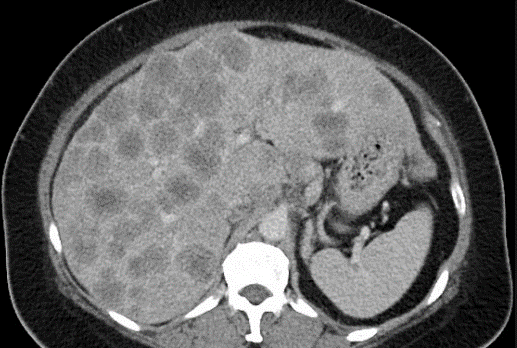

Вид метастазов в печени при проведении компьютерной томографии.

Для оценки эффективности NDV-GT исследователи использовали модель рака печени у обезьян, созданную с помощью технологии crispr/cas9. Эта модель позволяет более точно воспроизводить развитие и прогрессирование опухолей у человека, чем традиционные модели на животных. Результаты доклинических исследований показали превосходную способность ndv-gt уничтожать опухолевые клетки при внутривенном введении. Важно подчеркнуть, что использование модели на нечеловеческих приматах значительно повышает надежность прогнозов и вероятность успешного перевода результатов в клиническую практику. Это особенно актуально для онколитических вирусов, где вопросы безопасности и эффективности имеют критическое значение.